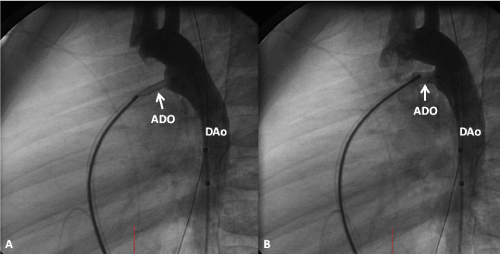

| Figure 7: Selected cine frame from aortic arch angiogram in lateral view demonstrating the position of the aortic disc of the Amplatzer duct occluder (ADO) (arrow) in the patent ductus arteriosus (A). Similar cine frame after opening the pulmonary end of the ADO (B). Both illustrate good position of the device components. In B, note small residual shunt thru’ the device and none parallel to it. This would indicate that the size of the device implanted is appropriate to the size of the ductus. Catheter with markers is seen in both A & B. DAo, descending aorta. |